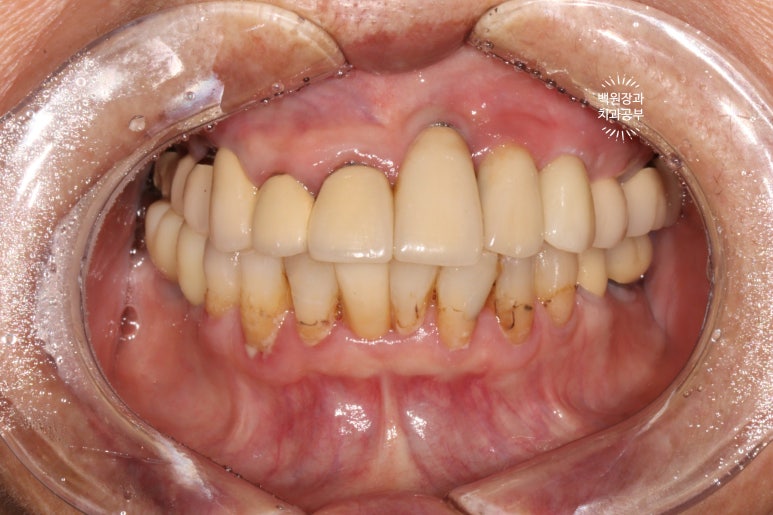

1주일이 지나 보철물을 모두 껴드렸습니다!

스트라우만 임플란트를 사용하여 수술하였던 어금니 부위에 임플란트 머리가 제작되었습니다!

상당히 많은 임플란트를 가지고 계시지만, 다행히 그 사이에 예쁘게 쏙 심어내었답니다 :)

약간 생긴게 다른데, 임플란트도 회사마다 보통 약 3-4가지 라인업이 있기 때문입니다. 스트라우만 임플란트의 경우 크게 Standard, BLT, BLX 라인이 있으니 형태가 달라도 놀라지 마세요! 상황마다 용도가 다를 뿐입니다.

예쁘게 제작된 임플란트 크라운은, 치아보다도 더 예쁘고 가지런한 모양을 보여준답니다.

어느게 스트라우만 임플란트인지 확인 가능하신가요..? ㅎ

화살표로 표시해놓은 것들이 이번에 새로 임플란트로 채워넣어진 자리입니다!

진짜 깔끔하고 예쁘게 마무리 되어서 너~무 뿌듯합니다 :)

정면 사진이 가장 드라마틱한데요,

일단 철저한 스케일링과 잇몸치료 그리고 함께 했던 착색제거술로 전반적으로 깨끗해진 구강내 환경을 보실 수 있어요!!! 다만, 아래 앞니에 있던 치아 목부위 레진들의 착색은 완전히 제거하지 못했답니다... 이는 다시 떼워야 해결이 되어요!

그리고 아래 앞니 한 곳은 지르코니아 크라운으로 씌워드렸고, 가지런히 깨끗깨끗~

위턱의 씹는면을 보시면, 스트라우만 임플란트로 아주 깔끔히 치료된 것을 보실 수 있습니다.

옛날에 치료받았던 스트라우만 임플란트는 이제 오래되어... 조금 깨지도 닳은 것은 보이나, 사실 기능하는데는 문제가 없었어요. 20년이 넘었음에도 이렇게 훌륭한 임상결과를 보이는 스트라우만 임플란트. 정말 최고임을 직접 보여주고 있었습니다. 진짜 올타임 넘버원 임플란트입니다.

아래 또한 깔끔하고 예쁘게 임플란트 크라운이 제작되었어요. 특징이라면 기존의 임플란트와 보철물을 묶어서 제작해드림으로써 음식이 끼는 것을 확실히 막아드렸다는 것입니다!